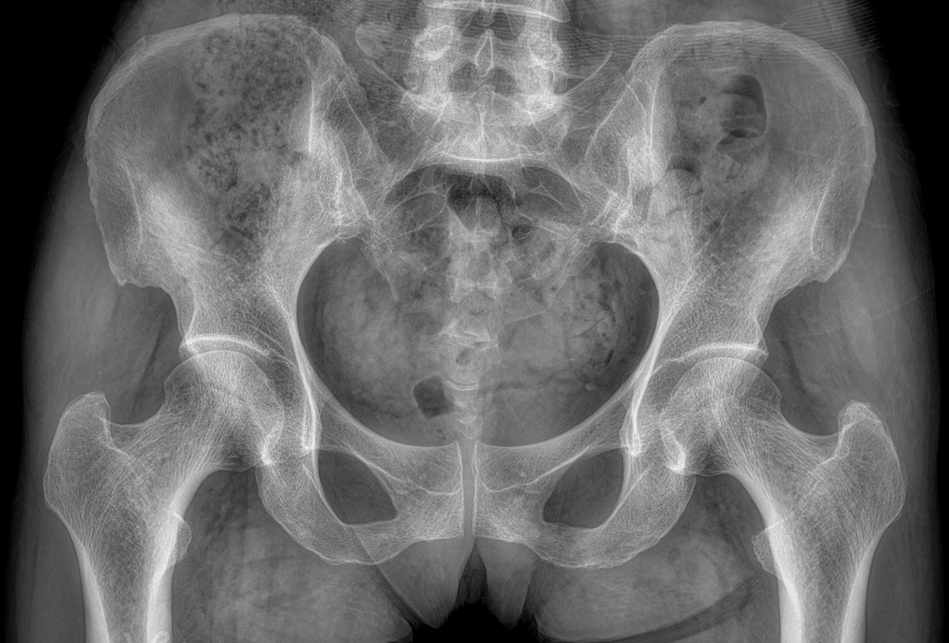

適用于全身各

部位透視檢查